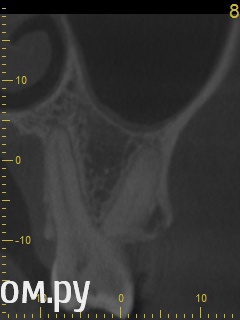

Анатолий М Опубликовано 21 апреля, 2014 Автор Поделиться Опубликовано 21 апреля, 2014 Снимок во время лечения делали? Коффердам и оптика использовались? На кт в тех срезах что Вы выложили кисты не вижу Снимки во время лечения делали три раза прицельные с иголками в каналах. Но они остались у врача. У меня их нет. Но она по ним кисты не видела. Коффердам использовали только при первом посещении когда вскрывали старую пломбу и прорабатывали каналы. При последующих посещениях при смене лекарст его не использовали так как кольцо на зубе плохо держалось и постоянно слетало. Плюс травмировало десну.Микроскоп использовали все три раза. По словам врача (врач высшей категории эндодонтист зав отделением):При вскрытии старой пломбы каналы практически не заполены цементирующим составом. Иструмент при вскрытии пломбы в каналы проваливался. Хотя стояла постоянна пломба. Из трех каналов лишь один был проработан до верхушки корня. Два других либо до половины либо на треть. Врачь полностью прошла все каналы и даже залезла за апекс. туда при первом пломбировании врач даже не пыталась лезть. При третьем посещении врач констатировала что каналы чистые. Никаких признаков инфекции нет. И белезненная перкуссия от чего то другого. Специально проводила ревизию каналов при втором и третьем посещении без анастезии что бы понять где болит. Но так и не поняла. Повела на консультацию к профессору в их стоматологи. Посмотрев контрольную КТ он сказал что там киста и надо удалять зуб! Похоже что мой врач с ним не очень согласна, хотя и спорить не стала поэтому отправила меня на консультацию к неврологу. Ниже срезы конрольного КТ после месяца лечения гидрооксидом кальция на воде. Срезы по дуге. Сделал как смог. Шаг срезов как я понимаю 1мм. Линия по перек дуги снимок номер 1 (см нумерацию в конце названия файла) Ссылка на комментарий

ромашечка Опубликовано 21 апреля, 2014 Поделиться Опубликовано 21 апреля, 2014 (изменено) Месяц хождения с гидроокисью кальция на воде никакого эфекта не дали. Зуб все еще под временной пломбой В каналах всё ещё гидроокись?? даже залезла за апекс?? Зачем? При третьем посещении врач констатировала что каналы чистые. Никаких признаков инфекции нет. И белезненная перкуссия от чего то другого. Специально проводила ревизию каналов при втором и третьем посещении без анастезии что бы понять где болит. Может у меня пробелы какие- но я не понимаю такой тактики. Болезненная перкуссия вполне может быть от того что каналы пустые или временно запломбированнны. Но мой взгляд , дотаточно качественно запломбировать ПОСТОЯННО каналы и проблема должна исчезнуть. Кисты не вижу. Изменено 21 апреля, 2014 пользователем ромашечка 1 Ссылка на комментарий

Анатолий М Опубликовано 22 апреля, 2014 Автор Поделиться Опубликовано 22 апреля, 2014 В каналах все еще гидроокись. Я просил врача поставить постоянную пломбу еще 3 недели назад и оставить зуб в покое. Но она говорит что боится закрывать зуб так как думает что там и вправду может быть киста. Хотя сама ее на снимках не видит. То что там есть киста мнение одного из 3 врачей которые смотрели меня в кресле и КТ во всех возможных срезах. Два остальных включая моего врача ничего подозрительного не видят. Врачь сказала ходи пока с временной пломбой. Проконсультируйся с неврологом. И если невролог потвердит что проблема стоматологиечская то 17 зуб кандидат на удаление. Вариант с депофорезом она впринципе не рассматривает.В любом случае всем спасибо за консультацию. Думаю что никакой кисты там и вправду нет. Попробую попасть к неврологу. А дальше будет видно. Ссылка на комментарий